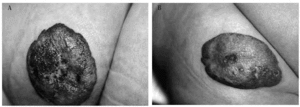

En el grupo de pacientes tratado con láser (tabla 2) las úlceras eran más profundas y provocaban dolor en todos los casos. Tres úlceras reepitelizaron tras una sesión; dos de ellas lo hicieron en las primeras 48 horas (figs. 1A y B). En la úlcera restante, que clínicamente era la más profunda de ambos grupos, de 3,2 x 2 cm de diámetro, localizada en la nalga y en fase de proliferación, se administraron tres tratamientos con láser aunque tras la primera sesión de láser, se inició la reepitelización por los bordes (figs. 2A y B). No se registró ninguna reacción adversa al tratamiento. Se observó una rápida mejoría del dolor en todos los casos en la primera semana tras el tratamiento, referida por la madre como una ausencia de dolor durante el baño, al dormir o con la alimentación.

Fig. 2.--A: hemangioma ulcerado en nalga antes del tratamiento con láser. B: reepitelización tras tres sesiones con láser.